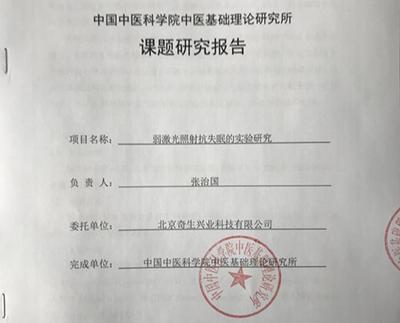

中国中医科学院研究证实结果

为了更好的改善人们的睡眠,北京奇生兴业科技有限公司和中国中医科学院共同研发大国康美弱激光理疗仪,它是通过照射头部的方式达到改善的效果,使它更安全、便捷、有效。而且大国康美弱激光理疗仪采用的还是最新的峰值波长685nm的弱激光,相比于其他的弱激光产品效果更强,见效更快,穿透更好。它不光可以帮您预防高血压,还可以降低血液粘稠度,改善睡眠,溶解脱落血管内的过多的糖类,疏通血管等诸多功效。它将会是是保障您健康的一大助力。